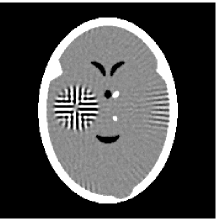

Furthermore, we used the classic ART iteration as the iteration operator in our numerical experiments. In order to compare the proposed superiorization algorithm with the classic superiorization algorithm, we applied the classic superiorization and -PP superiorization algorithm to two phantoms (see figure 1). The first one is the Shepp-Logan phantom[30], and the second one is the head phantom with a ghost which is invisible at 22 specified projection directions [10, 31]. In addition, we compare the performances of the two algorithms for the noiseless and noised data with different projections. In all experiments, the noised projection data was corrupted by additive Gaussian white noise with variance . We record the iterations, running time of program and mean square error (MSE) of different algorithms, where MSE is computed by

The reconstruction images from the noiseless projection data were shown in the Fig. 2. From Fig. 2, we can observe that the classic and the proposed algorithms can reconstruct images from the three projection data. In order to show the advantages of the proposed algorithm visually, the central vertical line of the differences between the reconstructed images and the original image are present in Fig. 3. We can observe that the -PP superiorization is more efficient than the classic superiorization in the aspect of suppressing the artifacts in the reconstructed images.